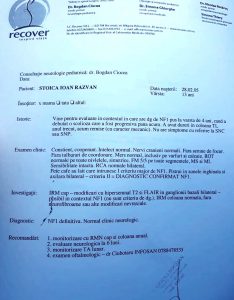

Răzvan Ioan Stoica are o curbură a coloanei vertebrale de 37 grade, iar aceasta se accentuează pe măsura trecerii timpului. Pentru ca lucrurile să nu se agraveze, el are nevoie cât mai urgent de o operație.

Răzvan a fost diagnosticat cu această boală de la vârsta de 4 ani și a purtat permanent un corset. Lucrurile s-au agravat însă, iar acum se impune intervenția chirurgicală.